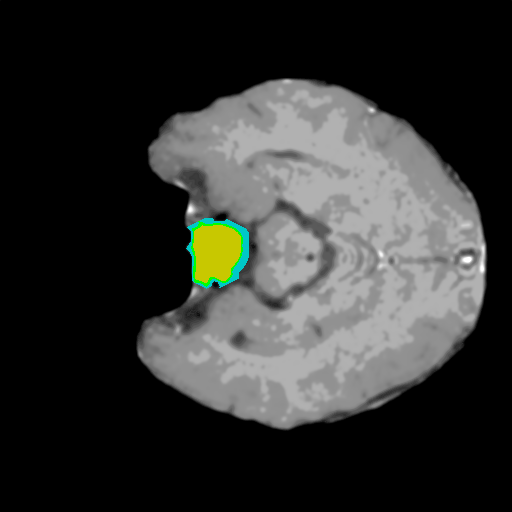

Extensive experiments have been performed in the current setup, and experimental outcomes are reported with the demonstration of numerical and statistical analyses using the proposed QFS-Net, QIS-Net [39], convolutional U-Net [18] and Residual U-Net (URes-Net) architectures [20]. The human expert segmented skull-tripped contrast enhanced DSC brain MR input image slices of size and ROIs are provided in Figure 5 as samples. The demonstration of QFS-Net segmented images followed by the essential post-processed outcome on the slice no. for class level with four distinct activation schemes () are shown in Figure 6. It is evident from the experimental data provided in Table LABEL:tab1 that the proposed QFS-Net performs optimally for the -connected quantum fuzzy pixel information heterogeneity assisted activation () with and gray scale set in comparison with other thresholding schemes and gray scale sets under the four evaluation parameters () [44]. The segmented tumors obtained using the proposed self-supervised procedure under class transition levels with four different thresholding schemes , , and are demonstrated in Figures 7- 8 for the class boundary sets and [39], respectively. The segmented images using the remaining two class boundary sets ( and ) [39] are provided in the supplementary materials section. The segmented ROIs describing the whole tumor region after the masking procedure using QIS-Net, U-Net and URes-Net are also reported in Figure 9.